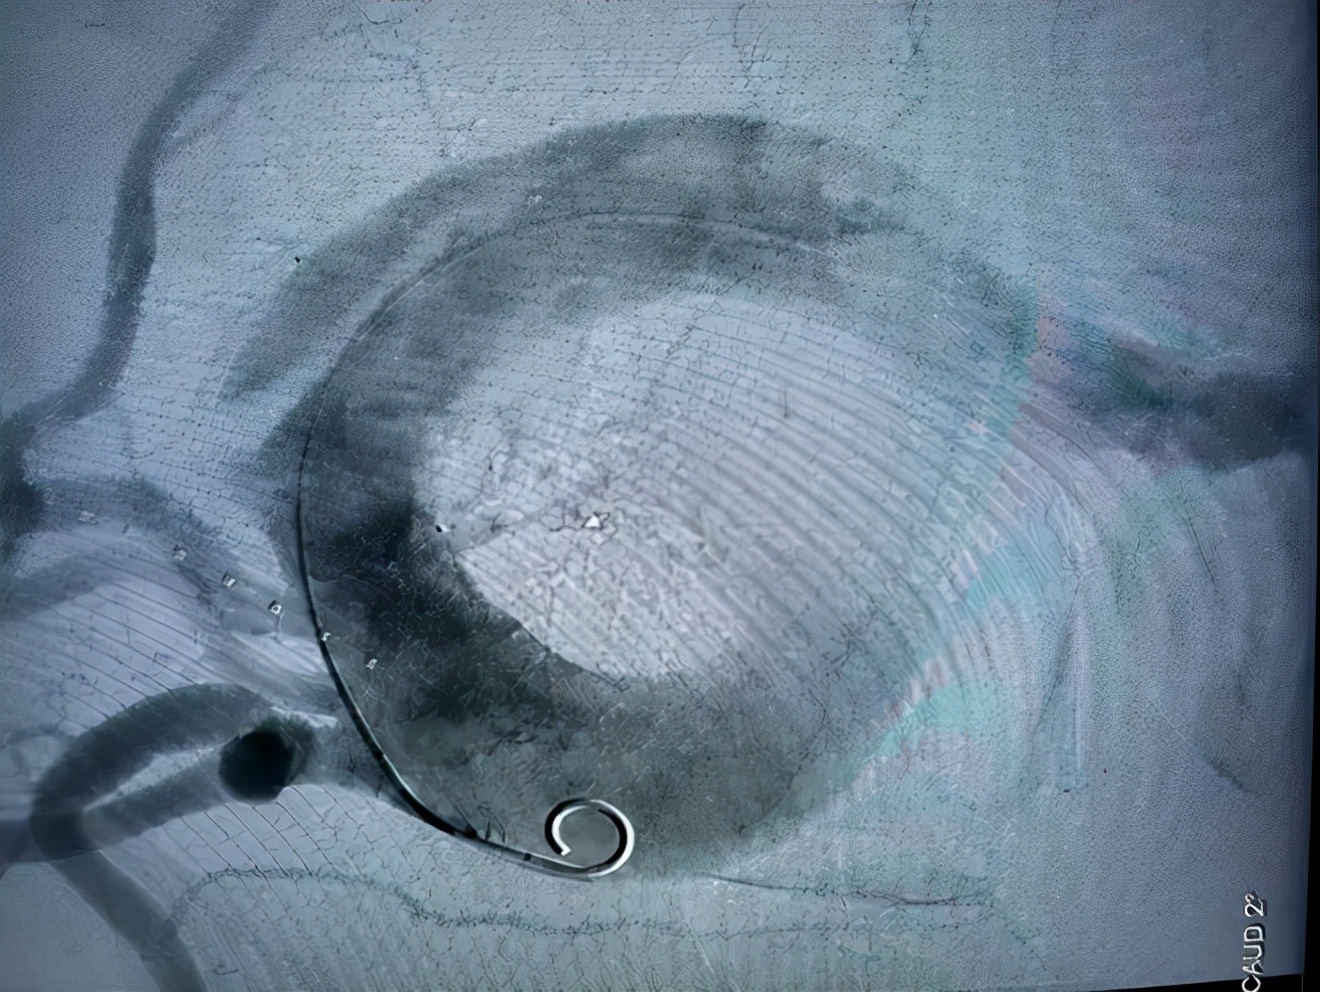

杨永久主任团队迅速对患者进行了 经皮胸主动脉腹覆膜支架腔内隔绝术 。术中通过造影见腹主动脉远端瘤样扩张,直径约3.0cm;左锁骨下动脉远侧主动脉夹层动脉瘤,血管破口距离锁骨下动脉1.5cm。从左侧股动脉穿刺依次置入血管缝合器、血管鞘、和胸主动脉带膜支架后,精确定位后释放支架以封闭动脉夹层破口,避免血管撕裂的进一步扩大。

(胸主动脉夹层动脉瘤术后:裂口被支架封闭,假腔闭塞,最终疤痕化)